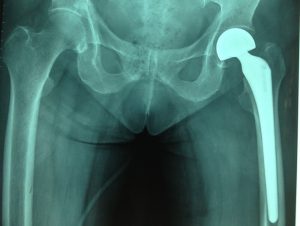

Ngày 29 tháng 12 năm 2016, kíp mổ của Khoa Ngoại bệnh viện huyện Củ Chi, do Bs.CKI. Trần Chánh Xuân mổ chính, đã tiến hành phẫu thuật theo phương pháp mà hội chẩn đã đề ra. Bệnh nhân được tê tủy sống và tê ngoài màng cứng, thời gian mổ kéo dài 45 phút, sau mổ bệnh nhân tỉnh táo, đo chiều dài hai chi dưới tương đương. Sau 6 giờ theo dõi phòng Hậu phẫu, tình trạng bệnh nhân ổn định, bệnh nhân được chuyển về Khoa Ngoại. Trong quán trình điều trị, chúng tôi sử dụng kháng sinh dự phòng và áp dụng phương pháp điều trị đau đa phương thức.

Thay khớp háng để điều trị những bệnh lý của khớp háng như thoái hoá khớp, tiêu chỏm, gãy cổ xương đùi, gãy liên mấu chuyển… ngày nay đã trở nên phổ biến. Những phương pháp thay khớp háng chính hiện nay là thay khớp háng toàn phần bao gồm thay chỏm xương đùi và ổ cối, hoặc thay bán phần là chỉ thay chỏm xương đùi đơn thuần. Hiện nay, do những ưu điểm vượt trội như kỹ thuật mổ tương đối đơn giản, biên độ vận động lớn, độ bền cơ học cao, khi hỏng cũng dễ dàng thay lại nên chỏm 2 dầu hay còn gọi là chỏm bipolar (Duocore) được sử dụng rộng rãi. Sau khi tiến hành thay khớp háng bán phần với chỏm bipolar bước đầu cho kết quả tốt.